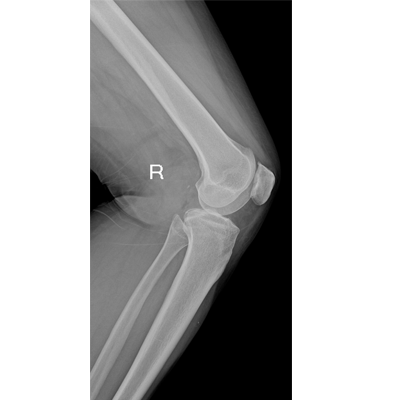

Clinical picture

臨床圖片